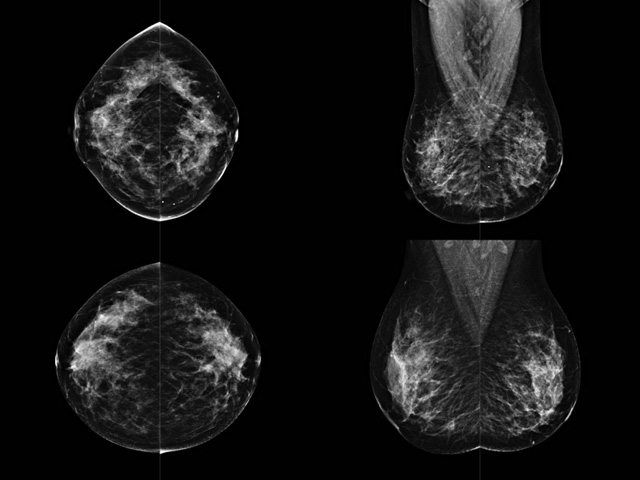

乳房检查时候要注意一些细节,需要更深入的了解这样才能使检查更准确。乳腺DR是乳腺癌的筛查诊断工具设备。是乳房方面检查的重要影像方法。它可以临床检查出早期的乳腺癌。可以判断良性恶性。因为它可以检查出早期的病变。对良性恶性检查的准确率达到90%以上。发病高峰年龄为45岁到54岁。50岁检查出来乳腺癌病患,可以让死亡率下降3成。所以30-40岁女性每年做一次乳腺DR检查。40岁以上就一年两次。如果家族史有乳腺癌的30岁以下也需要做检查。清晰显示乳腺各层组织严重的乳腺增生,乳腺炎,乳腺外伤也建议1年检查一次。极大提高了早期乳腺癌的敏感度和诊断率。